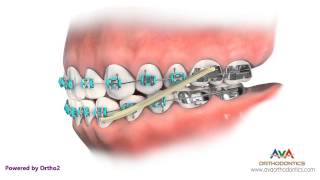

Orthodontic Treatment for Openbite - Rubber Bands

Orthodontic Treatment for Openbite - Rubber Bands How to Wear Rubber Bands - Vertical or Triangle Upper 3 Lower 3, 4

Orthodontic Treatment for Overjet (Overbite) - Rubber Bands How to Wear Rubber Bands - Class 2 Box on Upper 3, 4 Lower 4, 5

How to Wear Rubber Bands - Class 2 Box on Upper 3, 4 Lower 4, 5 Orthodontics Treatment for Underbite or Crossbite - Rubber Bands

Orthodontic Treatment for Overjet (Overbite) - Rubber Bands How to Wear Rubber Bands - Class 2 Box on Upper 3, 4 Lower 4, 5

How to Wear Rubber Bands - Class 2 Box on Upper 3, 4 Lower 4, 5 Orthodontics Treatment for Underbite or Crossbite - Rubber Bands